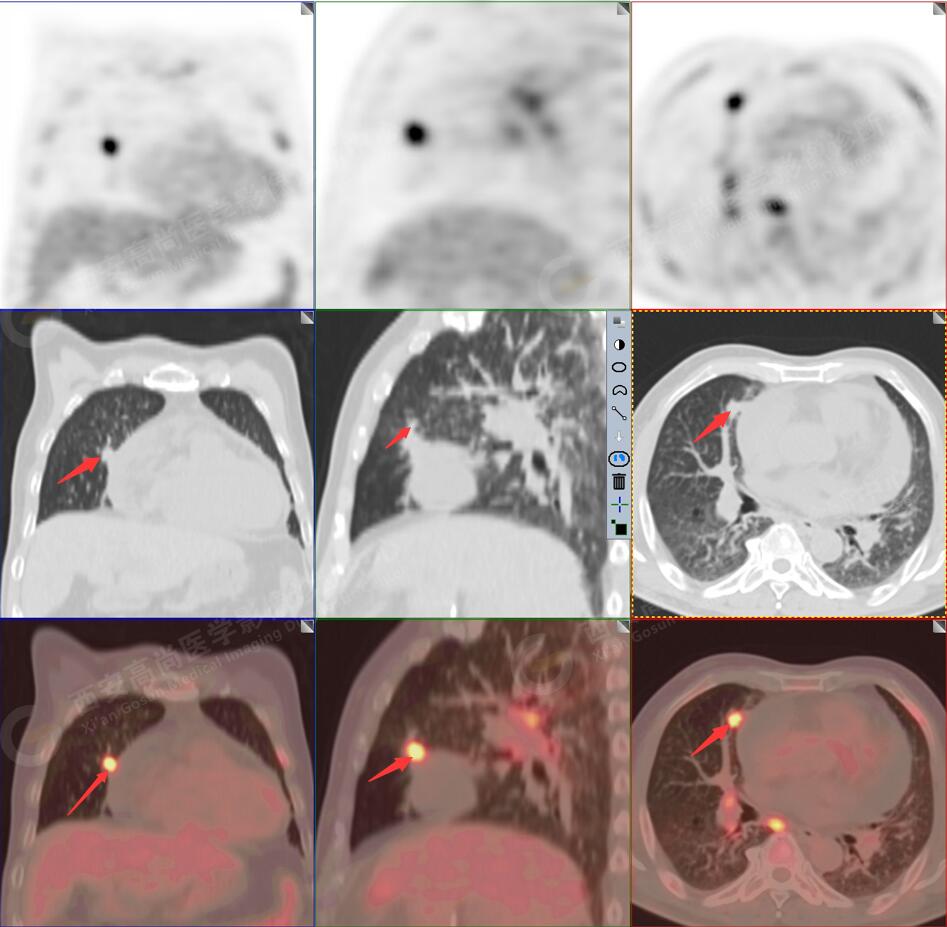

2.以下為全身多發(fā)轉移灶

2.雙肺內彌漫性分布大小不等實性小結節(jié)灶及粟粒狀高密度影,均未見FDG代謝明顯異常增高,均多考慮為癌性淋巴結炎及轉移性病變。

3.右側頸部(Ⅱ-Ⅴ區(qū))、右側腋窩區(qū)、右側肺門及縱隔(1R、1L、2、4、6、7組)、肝門區(qū)多發(fā)腫大淋巴結,呈不同程度異常增高,均考慮為淋巴結轉移。